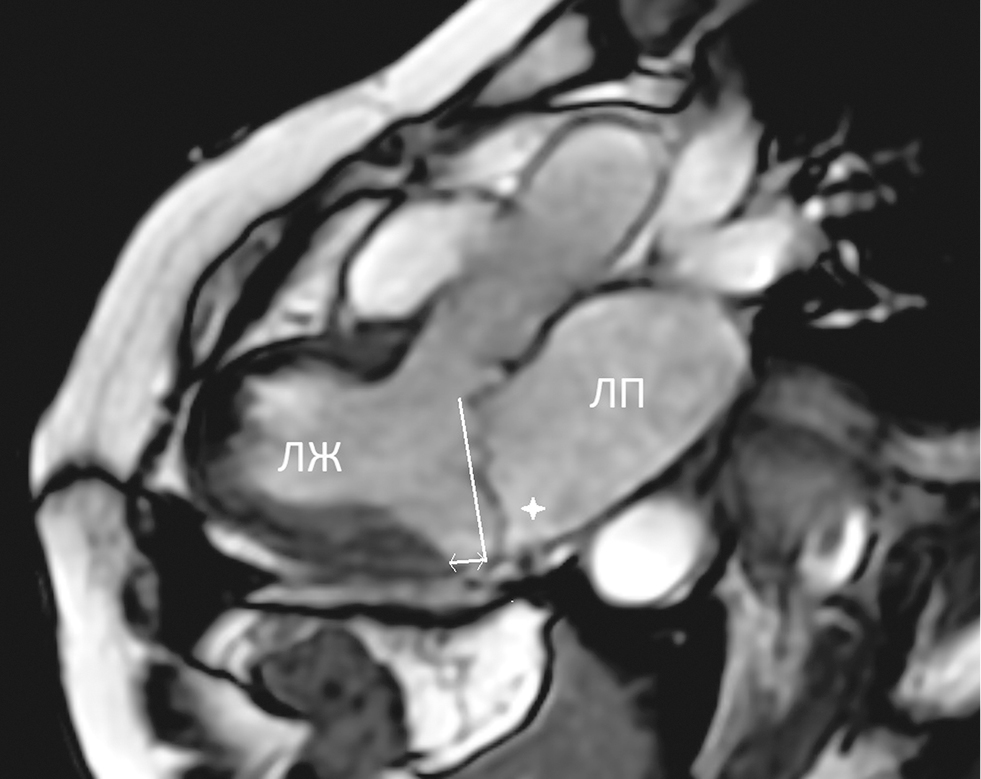

Prolapse of both cusps of the MV and MAD up to 8 mm at the level of the P3 segment was visualized (Fig. 2).

Fig. 2. Cardiac MRI, of end-systolic image in three-chamber view (Fiesta Cine). The thick arrow indicates the prolapse of the posterior leaf of the MV, the projection axis of the fibrous ring of the MV is carried out, the bidirectional arrow indicates the distance of the mitral annular disjunction

Рис. 2. Магнитно-резонансная томография сердца, конечно-систолическое изображение в трехкамерном виде (Fiesta Cine). Толстая стрелка указывает на пролапс задней створки митрального клапана, проведена проекционная ось фиброзного кольца митрального клапана, двунаправленная стрелка указывает расстояние митральной аннулярной дизъюнкции